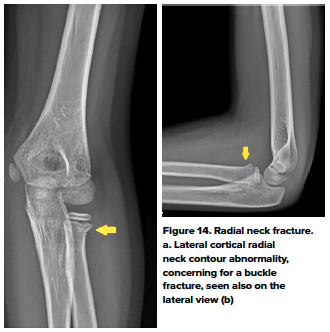

- Proximal Radial Fracture

- Proximal radial fractures can occur in the radial head or the radial neck. Most common mechanisms of injury include FOOSH with the elbow extended or posterior dislocation of the elbow. Patients present with tenderness over the radial head with pain localized to the lateral aspect of the elbow with pronation and supination. Radial neck fractures typically are classified as Salter Harris II fractures through the physis, and radial head fractures are intra-articular and typically occur in older children or adolescents.13 (Fig 14)